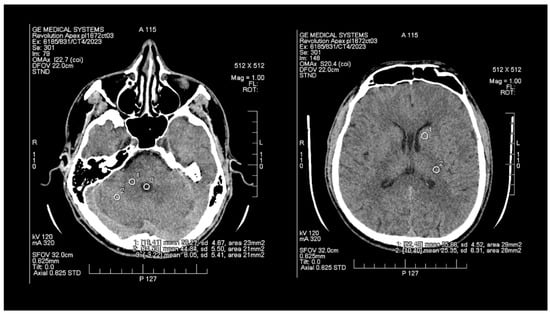

The objective assessment of image quality involved analyzing the signal-to-noise (SNR) and contrast-to-noise (CNR) ratios. To maintain consistency, a control variable was introduced in the form of manually set Regions of Interest (ROIs), which are analogous and predefined study areas in each pair of images. The average size of the ROI area was 24 mm2, with the smallest and the largest areas measuring 20 mm2 and 29 mm2, respectively. ROIs were positioned manually on the ASIR-V (Figure 1) reconstruction image, and then, duplicated at identical coordinates on the DLIR (Figure 2) reconstruction, which excluded potential deviations resulting from the lack of homogeneity of the measured tissues. The designation of the slice subject to the assessment was based solely on the anatomical factors of the patient. The first two ROIs were located in the white matter of the posterior limb of the internal capsule and the grey matter of the caudate nucleus, while the other two ROIs were positioned in the white and grey matter of the cerebellum. The fifth ROI was set in the cerebrospinal fluid of the fourth ventricle. To determine the signal level and noise, the mean CT number (mean) within the ROI and the standard deviation (SD) were taken into account.

Figure 1. Images of head CT with marked ROIs located in BGA (basal ganglia area) and PCF (posterior cranial fossa) obtained using FBP + ASIR.